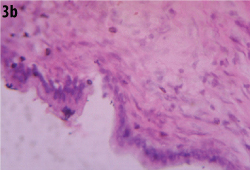

Gross examination showed an unilocular cystic lesion measuring 17 x 10 cm with a pale grey smooth cyst wall. [Table/Fig-2] of thickness that varied from 0.2 cm to 0.8 cm. On histology of the lesion showed a cyst wall internally lined by an epithelium of biliary type of columnar epithelium with focal pseudostratification and basally oriented nuclei with foci of apical mucin, no nuclear or cellular atypia and an underlying mesenchymal stroma that was resemblent of the ovarian stroma. Hence a diagnosis of biliary cystadenoma was offered [Table/Fig-3a,b] Immunohistochemistry of the tumour was positive for Cytokeratin in the epithelial cells [Table/Fig-4]. A final diagnosis of biliary cystadenoma was made.

Lesion composed of biliary type of epithelium with underlying mesenchymal stroma resembling ovarian stroma. (H&E, 100X).

Lesion composed of biliary type of columnar epithelium with focally pseudostratified areas and basally oriented nuclei and apical mucin with no atypia with mesenchymal stroma. (H&E, 400X).